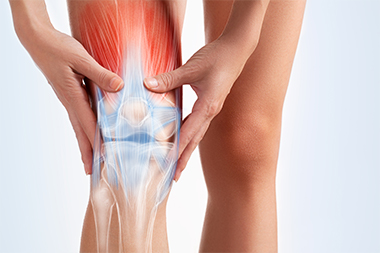

Le genou, l’une des articulations les plus sollicitées, nous permet de bouger tout en supportant une grande partie de notre poids.

Arthrose : usure du cartilage entraînant douleur et raideur.

Entorses ligamentaires : souvent liées au sport ou à des mouvements brusques.

Lésions méniscales : atteintes des coussinets qui amortissent les chocs.

Tendinites : douleur à l’avant du genou, fréquente chez les sportifs.